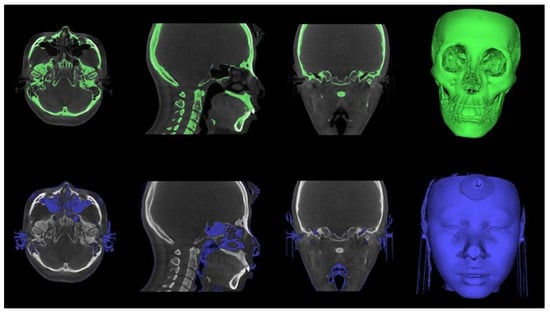

The Digital Imaging and Communications in Medicine (DICOM) files were converted into the. stl format, the standard file type representing the 3D surface geometry (Figure 3). Skeletal and soft tissue surfaces were constructed using the Invesalius open-access software (Renato Archer Information Technology Center, Campinas, Brazil). A specific density within the images that were derived from different shades of gray was customized by moving the threshold bars using an advanced 3D processing software (Geomagic Control X, 3D Systems, Rock Hill, SC, USA). An auto-alignment of the STereoLithography (STL) files obtained at T0 and T1 was performed, and the correspondence between the reference (T0) and measured (T1) data was checked (Figure 4).

Figure 3. Converting Dicom file to STL file with InVesalius software. The specific threshold value was applied to segment between the skull structures and soft tissues.